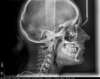

Canine incluse traitée avec des gouttières

Début de traitement